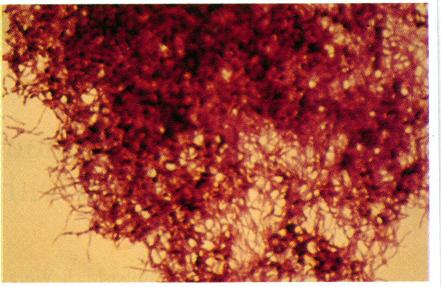

We report a case of endogenous Nocardia endophthalmitis in a patient with systemic lupus erythematosus (SLE). He developed a parafoveal lesion in the right fundus while on systemic corticosteroid and antibiotic treatment. Initially we suspected a fungal origin and treated him with antifungal drugs. The intraocular disease progressed without improvement and advanced to the vitreous cavity. Nocardia asteroides was found in a specimen obtained at pars plana vitrectomy and was also cultured from the same specimen. The intraocular infection was controlled by antibacterial drugs, though the visual acuity of the right eye was reduced to only light perception owing to heavy vitreous opacity and secondary cataract. This case is the first report of endogenous Nocardia endophthalmitis in Japan and also the first case of this disease reported from outside the United States of America.

我们报告一例系统性红斑狼疮(SLE)患者发生的内源性诺卡菌性眼内炎。该患者在接受全身性皮质类固醇和抗生素治疗期间,右眼眼底出现黄斑旁病变。起初我们怀疑是真菌性病因,并给予抗真菌药物治疗。眼内疾病持续进展且无改善,并蔓延至玻璃体腔。在经睫状体平坦部玻璃体切除术获取的标本中发现了星形诺卡菌,且同一标本培养出该菌。尽管由于严重的玻璃体混浊和继发性白内障,右眼视力降至仅存光感,但眼内感染通过抗菌药物得到了控制。该病例是日本首例内源性诺卡菌性眼内炎报告,也是美国以外地区报告的首例该疾病病例。